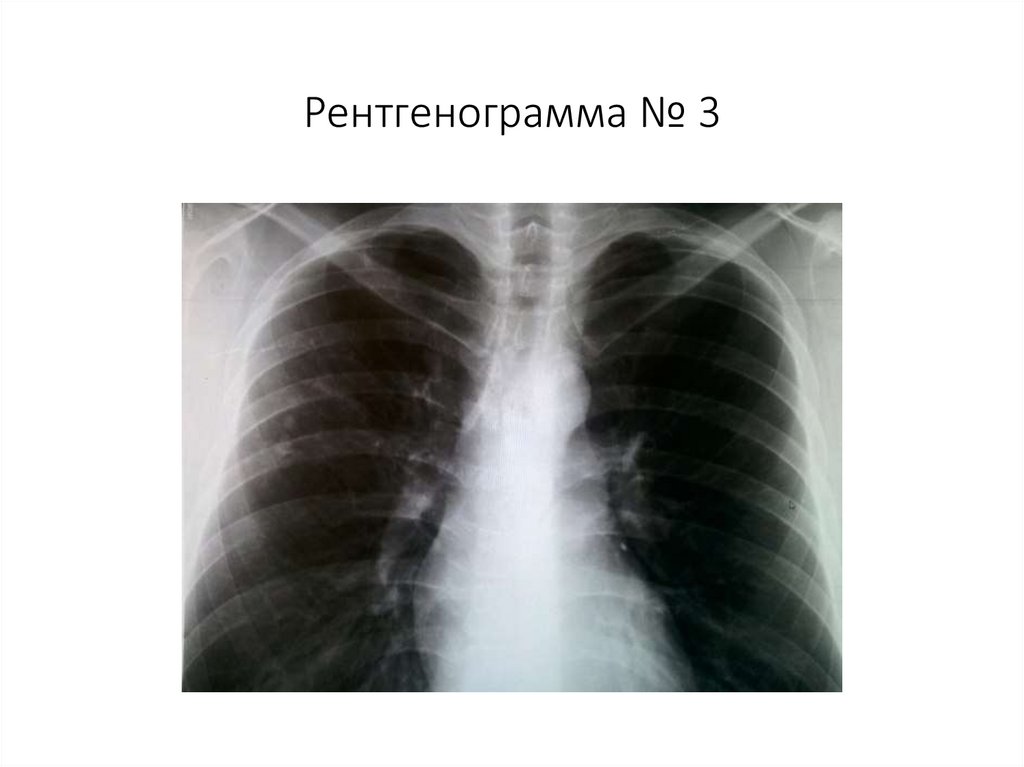

Рентгенограмма № 3

32. Рентгенограмма № 3